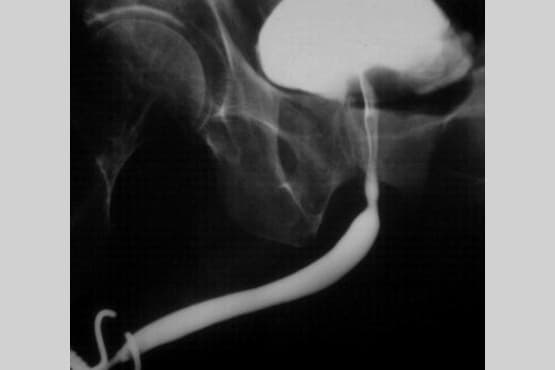

4. Retrograde / Ascending Urethrogram (RGU/AUG)

A radiological investigation in which a radio-opaque dye is injected into the urethra and the x-ray snap is taken.